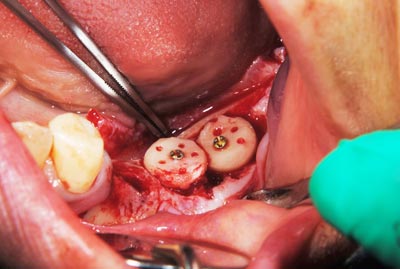

写真は、実際の手術の写真で、丸く採取された骨片が、スクリューで固定されています。

写真は、実際の手術の写真で、丸く採取された骨片が、スクリューで固定されています。

骨の移植手術後、移植した骨片が生着するのを数か月待って、インプラント埋入手術を行いました。写真はその時のもので、移植した骨が周囲の骨と一体化して、しっかりと骨が増えているのが分かります。

骨の移植手術後、移植した骨片が生着するのを数か月待って、インプラント埋入手術を行いました。写真はその時のもので、移植した骨が周囲の骨と一体化して、しっかりと骨が増えているのが分かります。